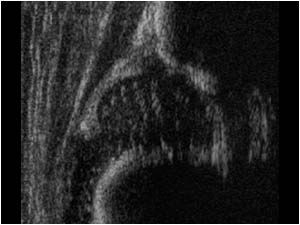

ΠΩΣ ΓΙΝΕΤΑΙ:η μέθοδος χρησιμοποιεί τα υπερηχητικά κύματα, τα ίδια που χρησιμοποιούνται για την παρακολούθηση της εγκύου καθ’ όλη τη διάρκεια της εγκυμοσύνης. Το νεογνό βρίσκεται σε ύπτια θέση με τα ισχία σε κάμψη και ο ηχοβολέας τοποθετείται στην έξω επιφάνεια του ισχίου.

ΓΙΑΤΙ ΓΙΝΕΤΑΙ: ο υπερηχογραφικός έλεγχος του νεογνικού ισχίου θεωρείται πλέον διεθνώς ως η καλύτερη μέθοδος διαλογής και ελέγχου των νεογνικών ισχίων προς αποκλεισμό της Αναπτυξιακής Δυσπλασίας του Ισχίου (ΑΔΙ). Η ΑΔΙ είναι μια ασυμπτωματική και ανώδυνη κατάσταση που προσβάλλει τα νεογνικά ισχία. Το νεογνό γεννιέται με εξαρθρωμένο ή ασταθές ισχίο. Η κατάσταση αυτή αν μείνει χωρίς αντιμετώπιση οδηγεί αργότερα σε μη φυσιολογική ανάπτυξη των οστικών και μη οστικών δομών της άρθρωσης του ισχίου(κοτύλη, κεφαλή μηριαίου, επιχείλιος χόνδρος, αρθρικός υμένας και μαλακά μόρια). Μπορεί να μην είναι εμφανείς οι προσβολές των δομών αυτών άμεσα, όμως με την πάροδο των χρόνων και τελικά στην ενηλικίωση εμφανίζεται επώδυνη αρθρίτιδα και χωλότητα του προσβεβλημένου σκέλους. Η οριστική αντιμετώπιση τότε δεν είναι άλλη από την ολική αρθροπλαστική του ισχίου.